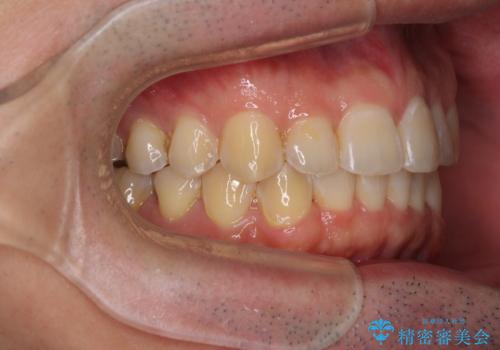

ディープバイトと叢生を解消 インビザライン矯正

- 前歯のデコボコを強い咬みしめを気にして来院された患者様です。

インビザラインを用いて、前歯の叢生を解消するとともに、ディープバイトを改善していくこととしました。

ディープバイトが改善されたことで、顎への負担が軽減され、更には上顎前歯の突出感も改善することができました。

矯正治療後には欠けてしまった修復物をセラミックインレーにて修復治療しました。